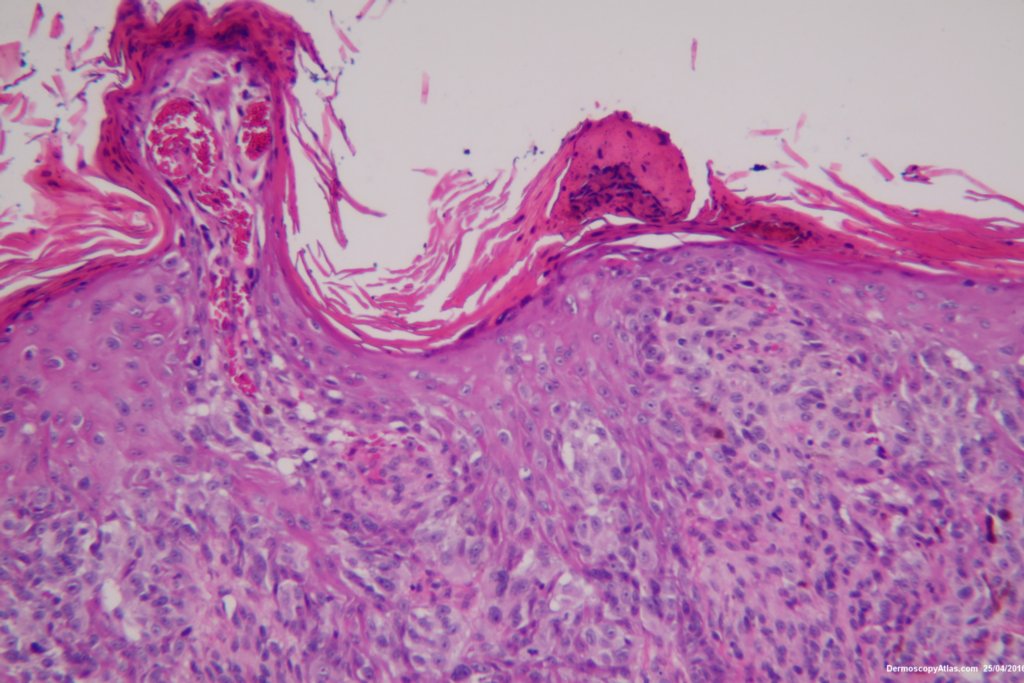

This 57 years old male presented with a lesion on his thigh that he said had only been present for 6 weeks. It looked and felt keratotic and had a bluish discolouration associated with it. It was thought to be an irritated Seborrhoeic keratosis perhaps with some bleeding into it to account for the blue colour.

The shave biopsy was reported as a level 4 Invasive melanoma 1.7 mm thick with 3 mitoses per high powered field. There were no groin glands enlarged clinically.